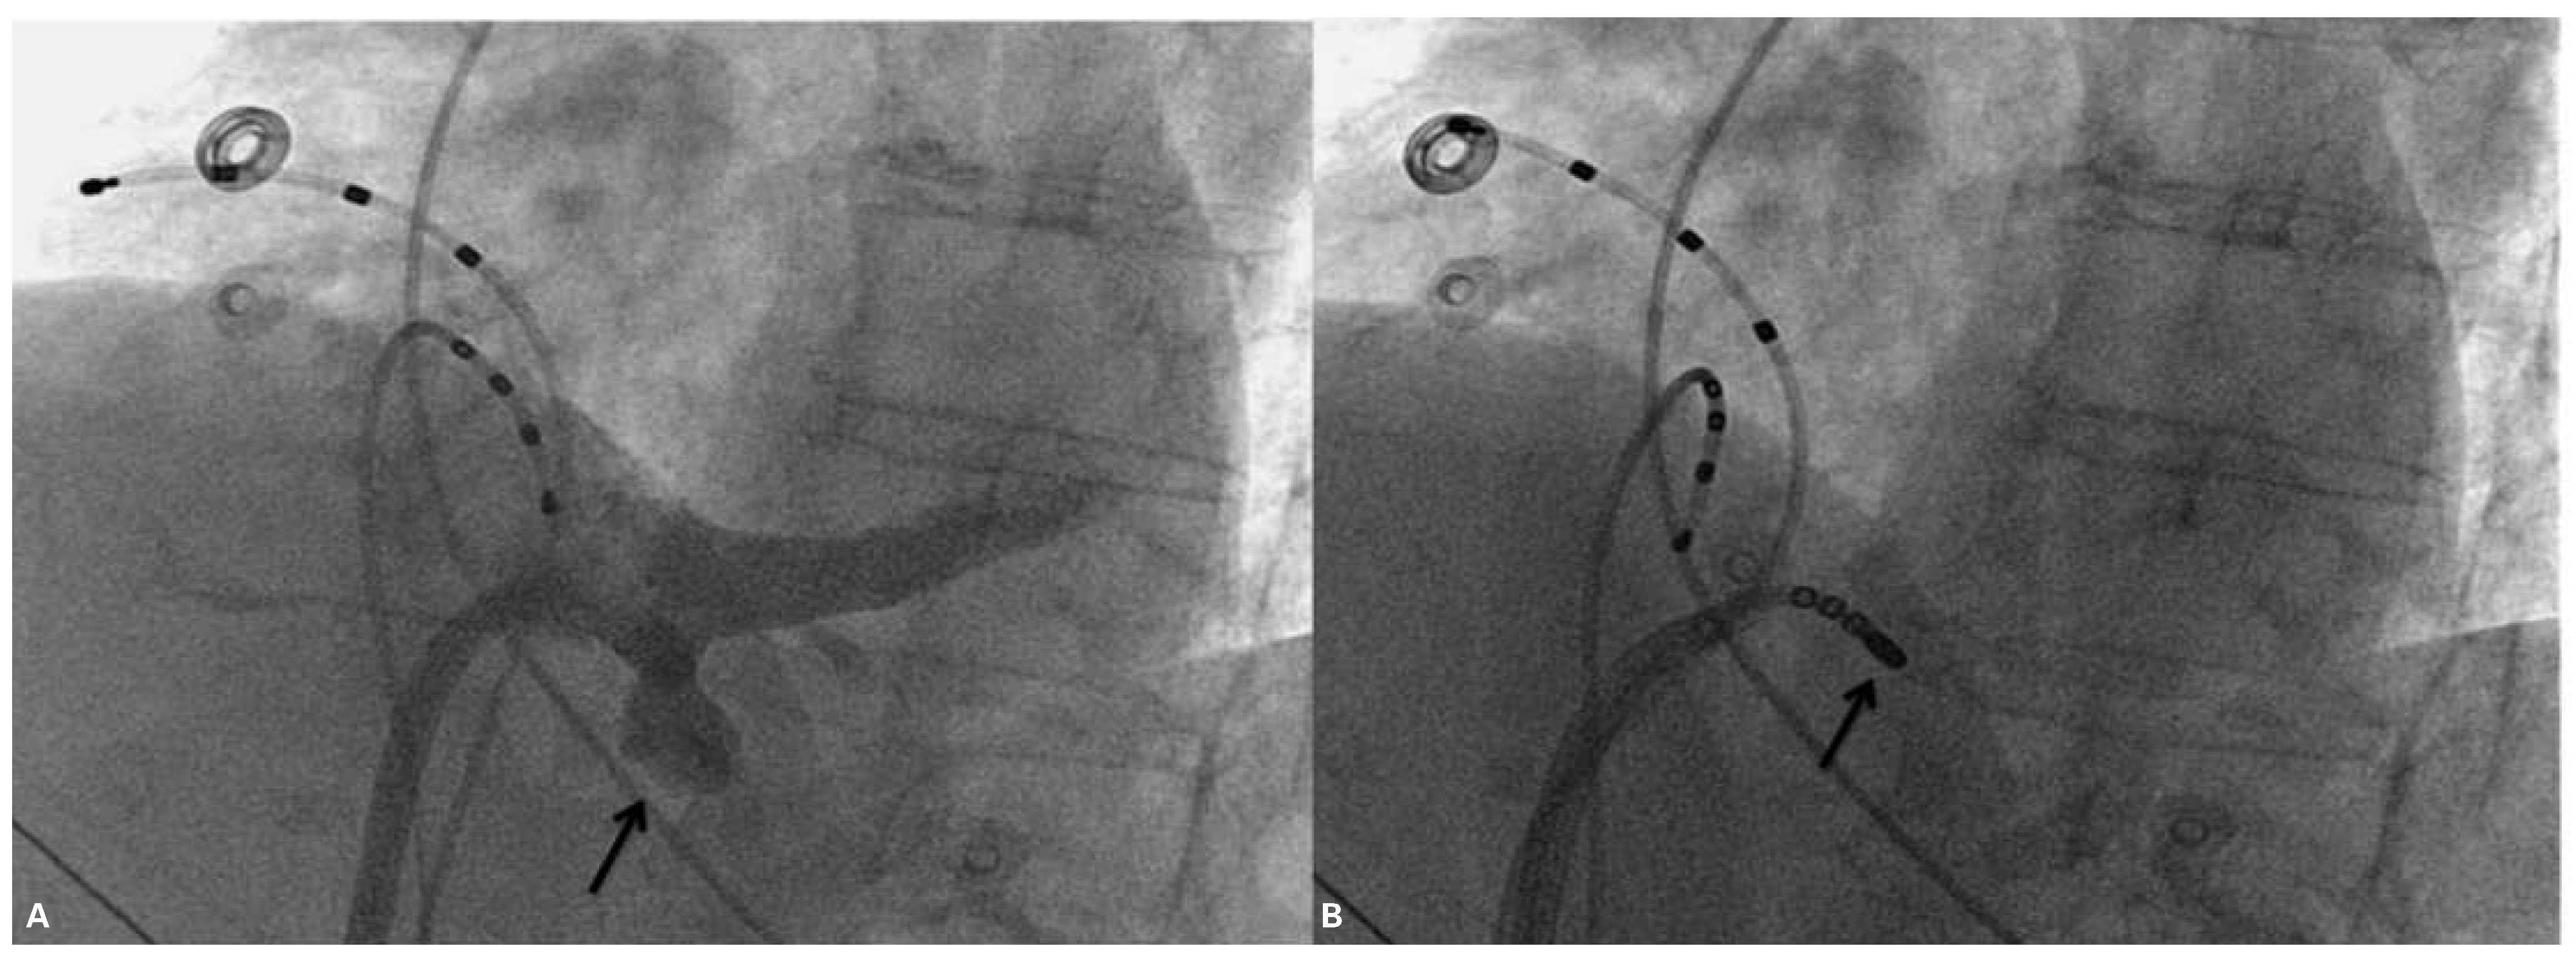

Wolff-Parkinson-White Syndrome and Diverticulosis of the Heart?

Case presentation

Comment